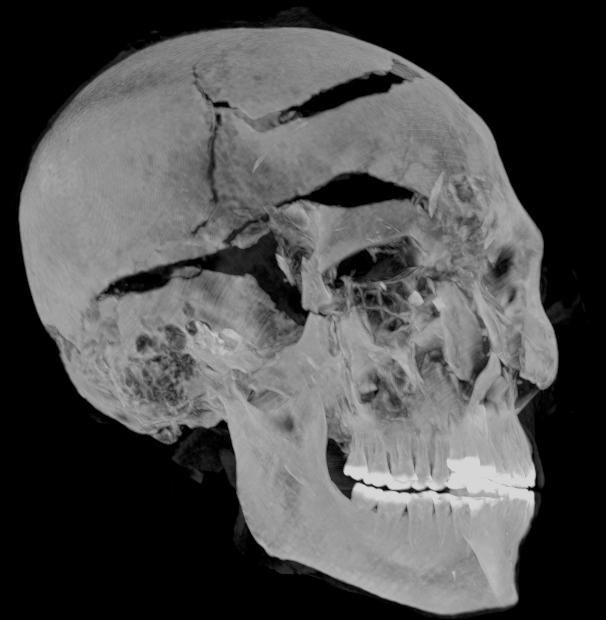

Cụ thể, kết quả chụp CT cho thấy phần mặt của xác ướp có nhiều vết thương. Những người thợ ướp xác cố gắng che những vết thương này khi bảo quản thi hài nhà vua.

Vào thời điểm qua đời, pharaoh Seqenenre Taa II có một vết thương lớn trên trán, vết cắt xung quanh mắt và má, một vết đâm ở đáy hộp sọ. Hộp sọ của nhà vua tách rời khỏi phần còn lại của thi hài.

Với những vết thương này, các chuyên gia nhận định pharaoh Seqenenre Taa II bị kẻ thù bao vây và tấn công từ nhiều phía. Họ sử dụng dao găm, rìu và giáo tấn công nhà vua Ai Cập đến chết.